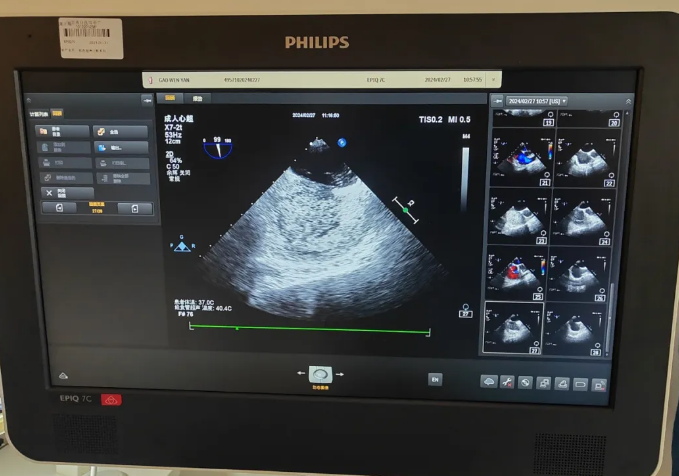

周二上午,星城院区功检科在特聘专家、北京宣武医院王彩荣教授的指导下,首先给患者行确诊卵圆孔未闭的常规检查——经胸心脏超声和经食道心脏超声,但均未发现卵圆孔未闭,考虑可能是因为卵圆孔未闭缺损太小,随后王彩荣教授团队又给患者进一步完善右心声学造影,经专业团队的熟练操作,十分钟就完成了造影,明确诊断为“卵圆孔未闭”,缺损仅仅只有2mm,为患者长期的头痛问题找到病因。